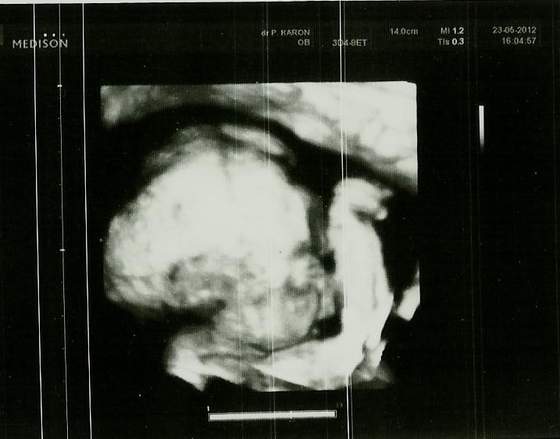

Za to dzisiaj byłam na usg, to było najkrótsze usg pod słońcem, trwało może ze 2 minuty, na nfz, rany jak dobrze, że są prywatne!

nie widziałam monitorka, nic, dowiedziałam się tylko, że wszystko ok, wyniki odbiorę u gin, ale ogólnie Maluszek nadal jest chłopcemi waży już 1100 ! wow już ma ponad 1 kg, kawał chłopaka!

z ułożenia głowką w dół ma teraz poprzeczne, ale się wierci ciągle![]()